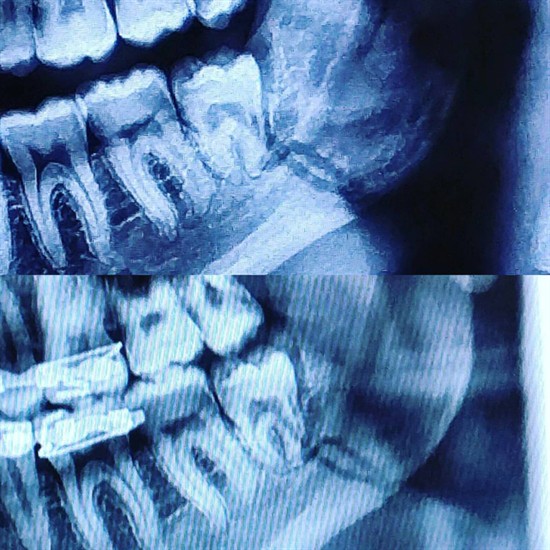

Here is a comparison of my x-rays one week apart. There is very good progress after only week as both the top and bottom of the fracture have almost fully calcified. Also the space of the non-union has decreased a good amount.